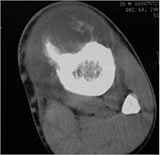

CT Scan:

- Periosteal reaction evident and mass on surface of bone

- May demonstrate subtle mineralization in tumor